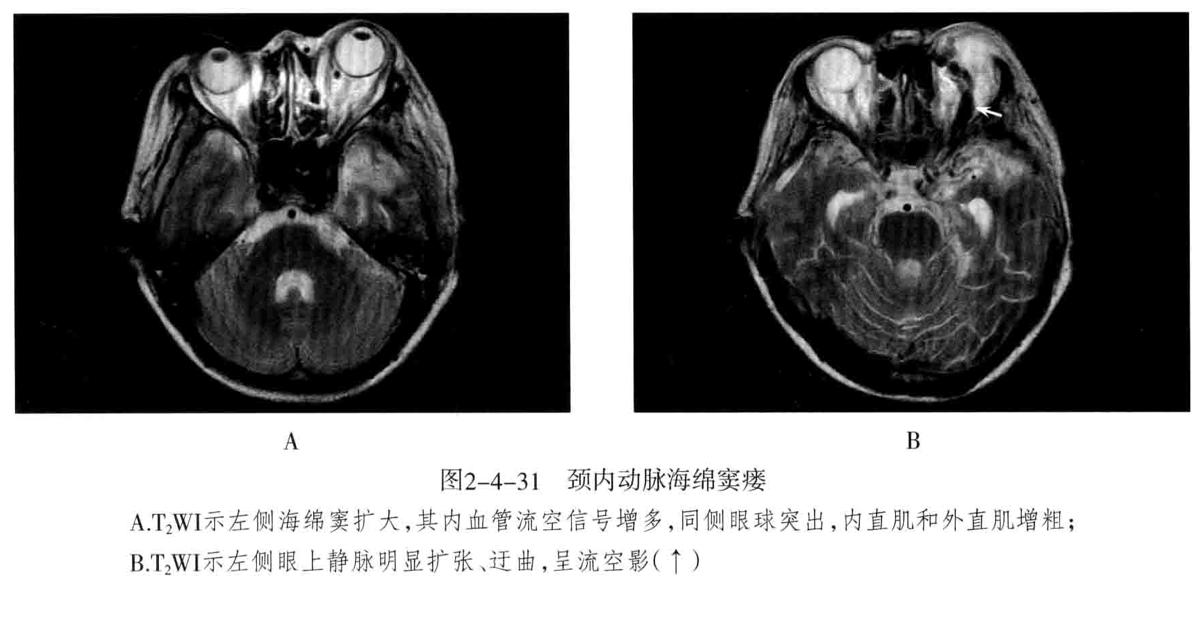

颈内动脉海绵窦瘘: 定义:指海绵窦段的颈内动脉及其分支破裂,与海绵窦之间形成动静脉的异常沟通所引起的一组神经眼科综合征。75%以上由外伤性引起,多为单侧发病,眼部征像多出现在患侧。

- CT表现为海绵窦增宽,增强扫描海绵窦明显强化,眼上静脉增粗扭曲。CTA可清楚显示扩张的眼上静脉和海绵窦。眼外肌充血增粗和眼球突出。

- MRI:海绵窦扩大,海绵窦内血管影增多,且迂曲、粗大、不规则。同侧眼上静脉明显扩张,呈迂曲的流空信号。眼外肌增粗充血和眼球突出。需与海绵窦肿瘤性病变鉴别。

- DSA检查:颈内动脉海绵窦段、海绵窦及增粗的眼上静脉 于 动脉期同时显影;